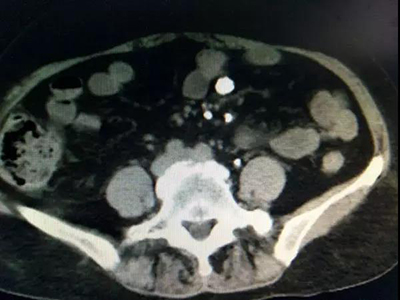

入院后彩超检查显示:左肾窦内可见数个大小不等的结石,最大的2.6 x1.9厘米,左输尿管上段距肾门2.5厘米处可见一大小约1.9厘米的结石。肾盂静脉造影显示:左肾及左侧输尿管上段多发结石,伴左侧肾盂、肾盏扩张;右肾缺如。CT检查显示:左肾肾盂、肾盏多发不规则高密度影,部分形成肾盏铸型,边缘锐利,CT值780—1500HU,左肾多发类圆形低密度影,右肾缺如。心电图检查:T波改变。胸片提示:两肺纹理增多、心影增大。经详细检查最终确诊为:左肾多发结石、左输尿管多发结石、左肾多囊肾、右肾缺如、高血压Ⅱ级。